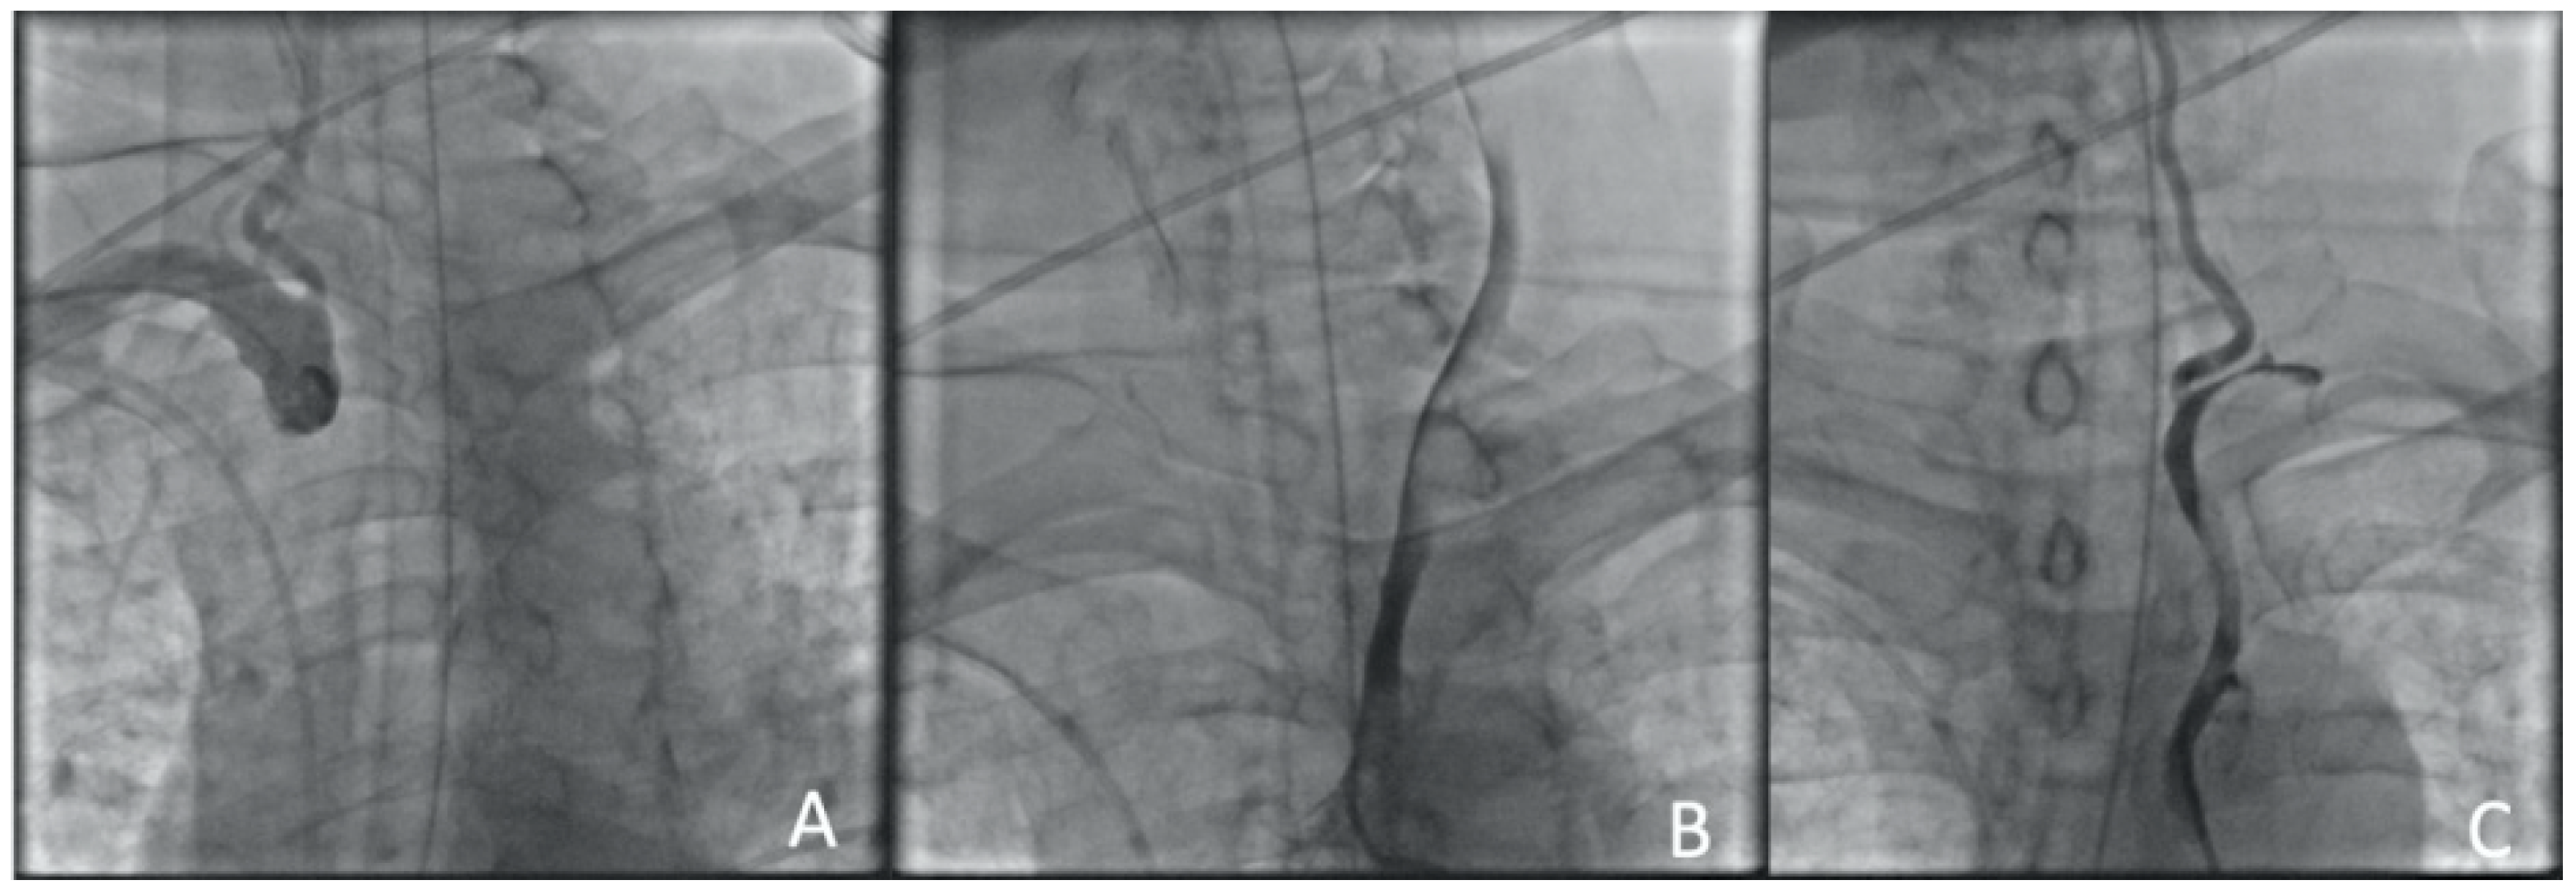

TLT was started immediately. Considering the progressive increase in neurological deficit within 10 min from the start of TLT, it was decided to perform a combined reperfusion. The patient was taken to the cath lab 60 min after the onset of the symptoms. The first difficulty was performing a puncture of the right femoral artery. Despite the presence of a clear pulsation and the pulsating blood flow from the needle, the guidewire could not be placed in the artery lumen. To perform the immediate reperfusion, it was decided to change access on the left side, which was performed without technical difficulties. Angiography showed a total aortic dissection from the bifurcation to the right iliac artery (Figure 10). Selective cerebral angiography showed brachiocephalic trunk (BCT) occlusion, left CCA occlusion, and dynamic left subclavian artery compression. The patient also demonstrated a stealphenomenon along the vertebral arteries from left to right (Figure 10).

Figure 10.

Clinical Case 2, Patient S., male, 60 years old. Aortic arch angiography. (A) BCT dissection with right CCA and right subclavian artery occlusion; (B) left CCA angiography determines the true lumen compression and a stop of blood flow through the ICA; (C) left subclavian artery angiography determines the stealphenomenon throughout the vertebral arteries.